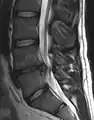

L'imagerie par résonance magnétique peut montrer la hernie, le canal vertébral, les nerfs, les tissus environnants. Les tissus mous sont les mieux analysés par cet examen qui est le plus performant pour le diagnostic de hernie discale. Les images pondérées en T2 montrent clairement la hernie.

IRM lombosacrée sagittale montrant une hernie discale de niveau L4-L5. IRM lombosacrée sagittale montrant une hernie discale de niveau L4-L5.

IRM lombaire sagittale montrant une hernie discale de niveau L4-L5. IRM lombaire sagittale montrant une hernie discale de niveau L4-L5.